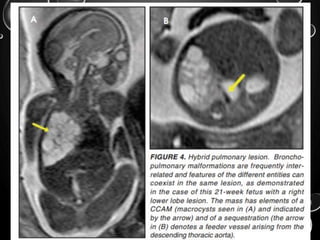

CONGENITAL CYSTIC ADENOMATOID

MALFORMATIONS

• (CCAM) ARE THE MOST COMMONLY DIAGNOSED

PRENATAL LUNG MALFORMATIONS AND

ACCOUNT FOR APPROXIMATELY 30% TO 40% OF

ALL CONGENITAL ANOMALIES.

• THEY ARE CHARACTERIZED BY AN ABNORMAL

BRANCHING OF IMMATURE BRONCHIOLES AND A

LACK OF ALVEOLAR DEVELOPMENT, RESULTING

IN A MASS THAT MAY CONTAIN BOTH CYSTIC

AND SOLID COMPONENTS.

• CCAMS COMMUNICATE WITH THE

TRACHEOBRONCHIAL TREE.

• BY MR, CCAMS PRESENT PRENATALLY AS HOMOGENEOUS OR

HETEROGENEOUS SOLID OR CYSTIC MASSES WITH BLOOD

USUALLY SUPPLIED BY THE PULMONARY CIRCULATION.

BRONCHOPULMONARY

SEQUESTRATIONS

• (BPS) INVOLVES ABNORMAL, NONFUNCTIONING

PULMONARY TISSUE THAT DOES NOT CONNECT WITH THE

NORMAL TRACHEOBRONCHIAL TREE AND RECEIVES ITS

VASCULAR SUPPLY FROM THE SYSTEMIC CIRCULATION.

• BY MR, THE CHARACTERISTICS OF BPSS ARE SIMILAR TO

CCAMS: SOLID, T2 HYPERINTENSE MASSES, USUALLY WELL

DEFINED.

• DIFFERENTIATION BETWEEN CCAM AND INTRATHORACIC BPS

MAY BE CHALLENGING, BUT IDENTIFICATION OF A SYSTEMIC

ARTERIAL SUPPLY, MOST COMMONLY THE AORTA, INDICATES

A DIAGNOSIS OF SEQUESTRATION.